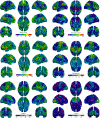

Disorders of consciousness are a heterogeneous mixture of different diseases or injuries. Although some indicators and models have been proposed for prognostication, any single method when used alone carries a high risk of false prediction. This study aimed to develop a multidomain prognostic model that combines resting state functional MRI with three clinical characteristics to predict one year-outcomes at the single-subject level. The model discriminated between patients who would later recover consciousness and those who would not with an accuracy of around 88% on three datasets from two medical centers. It was also able to identify the prognostic importance of different predictors, including brain functions and clinical characteristics. To our knowledge, this is the first reported implementation of a multidomain prognostic model that is based on resting state functional MRI and clinical characteristics in chronic disorders of consciousness, which we suggest is accurate, robust, and interpretable.